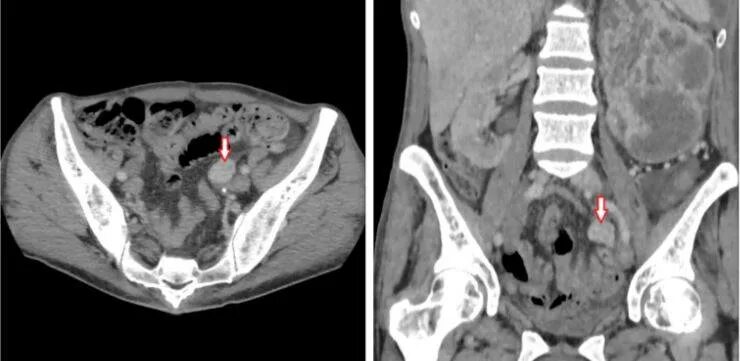

Где можно сделать кт малого таза